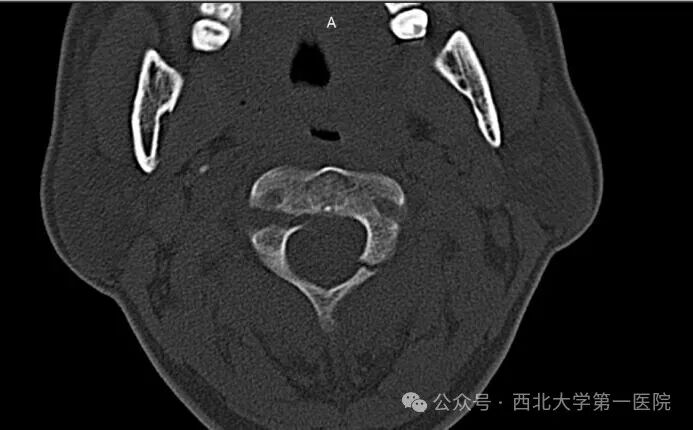

本例患者张先生(化名)遭遇汽车追尾事故。事故发生时,巨大的暴力瞬间作用于颈椎,导致其颈部剧痛、活动严重受限。被紧急送至西北大学第一医院后,急诊颈椎CT三维重建检查明确诊断为Hangman骨折(Levine - Edwards分型Ⅱ型)。影像资料显示,张先生的第二颈椎(枢椎)两侧椎弓根骨折,椎体向前移位,颈椎稳定性遭到严重破坏。脊髓作为人体的“神经总电缆”,在骨折断端间承受着巨大的压迫和牵拉风险,随时可能引发呼吸心跳骤停或四肢瘫痪等严重后果,情况万分危急。

患者伤后CT冠状面显示,C2椎体双侧椎弓根均有骨折,属于不稳定的Ⅱ型骨折。对于此类患者,时间就是生命,速度关乎功能恢复。脊柱外科(骨科三病区)迅速启动应急预案,为患者佩戴头颈胸支具严格制动,并立即组织多学科术前讨论。保守治疗虽有一定尝试空间,但对于这种明显移位的Ⅱ型骨折,长期卧床牵引不仅愈合率低,还存在滑脱加重的高风险,犹如一颗“定时炸弹”。经过严谨、审慎的评估,医疗团队最终决定为张先生实施“后路颈椎切开复位、C2椎弓根螺钉 + C3侧块螺钉钉棒系统内固定融合术”。